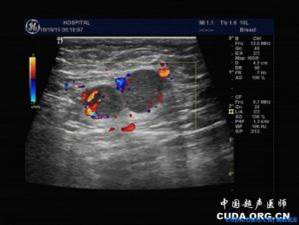

乳腺疾病

•3 乳腺肿瘤:良性 --纤维腺瘤

恶性 --乳腺癌无痛性肿块